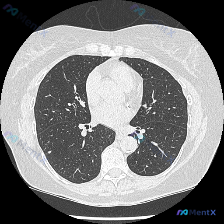

双肺上叶对称磨玻璃影:过敏性肺炎还是非典型病原体感染?

看到一个胸部CT肺窗的影像资料,整理了一下思路,跟大家分享讨论。 病例资料: - 主诉:无明确急性感染症状(如高热)。 - 现病史:患者可能有轻微咳嗽,但无典型肺炎症状。 - 影像检查:胸部CT肺窗横断面,显示双肺上叶外周带对称性分布的磨玻璃影,边界模糊。无实变、空洞或钙化,气道通畅,胸膜光滑,无胸...